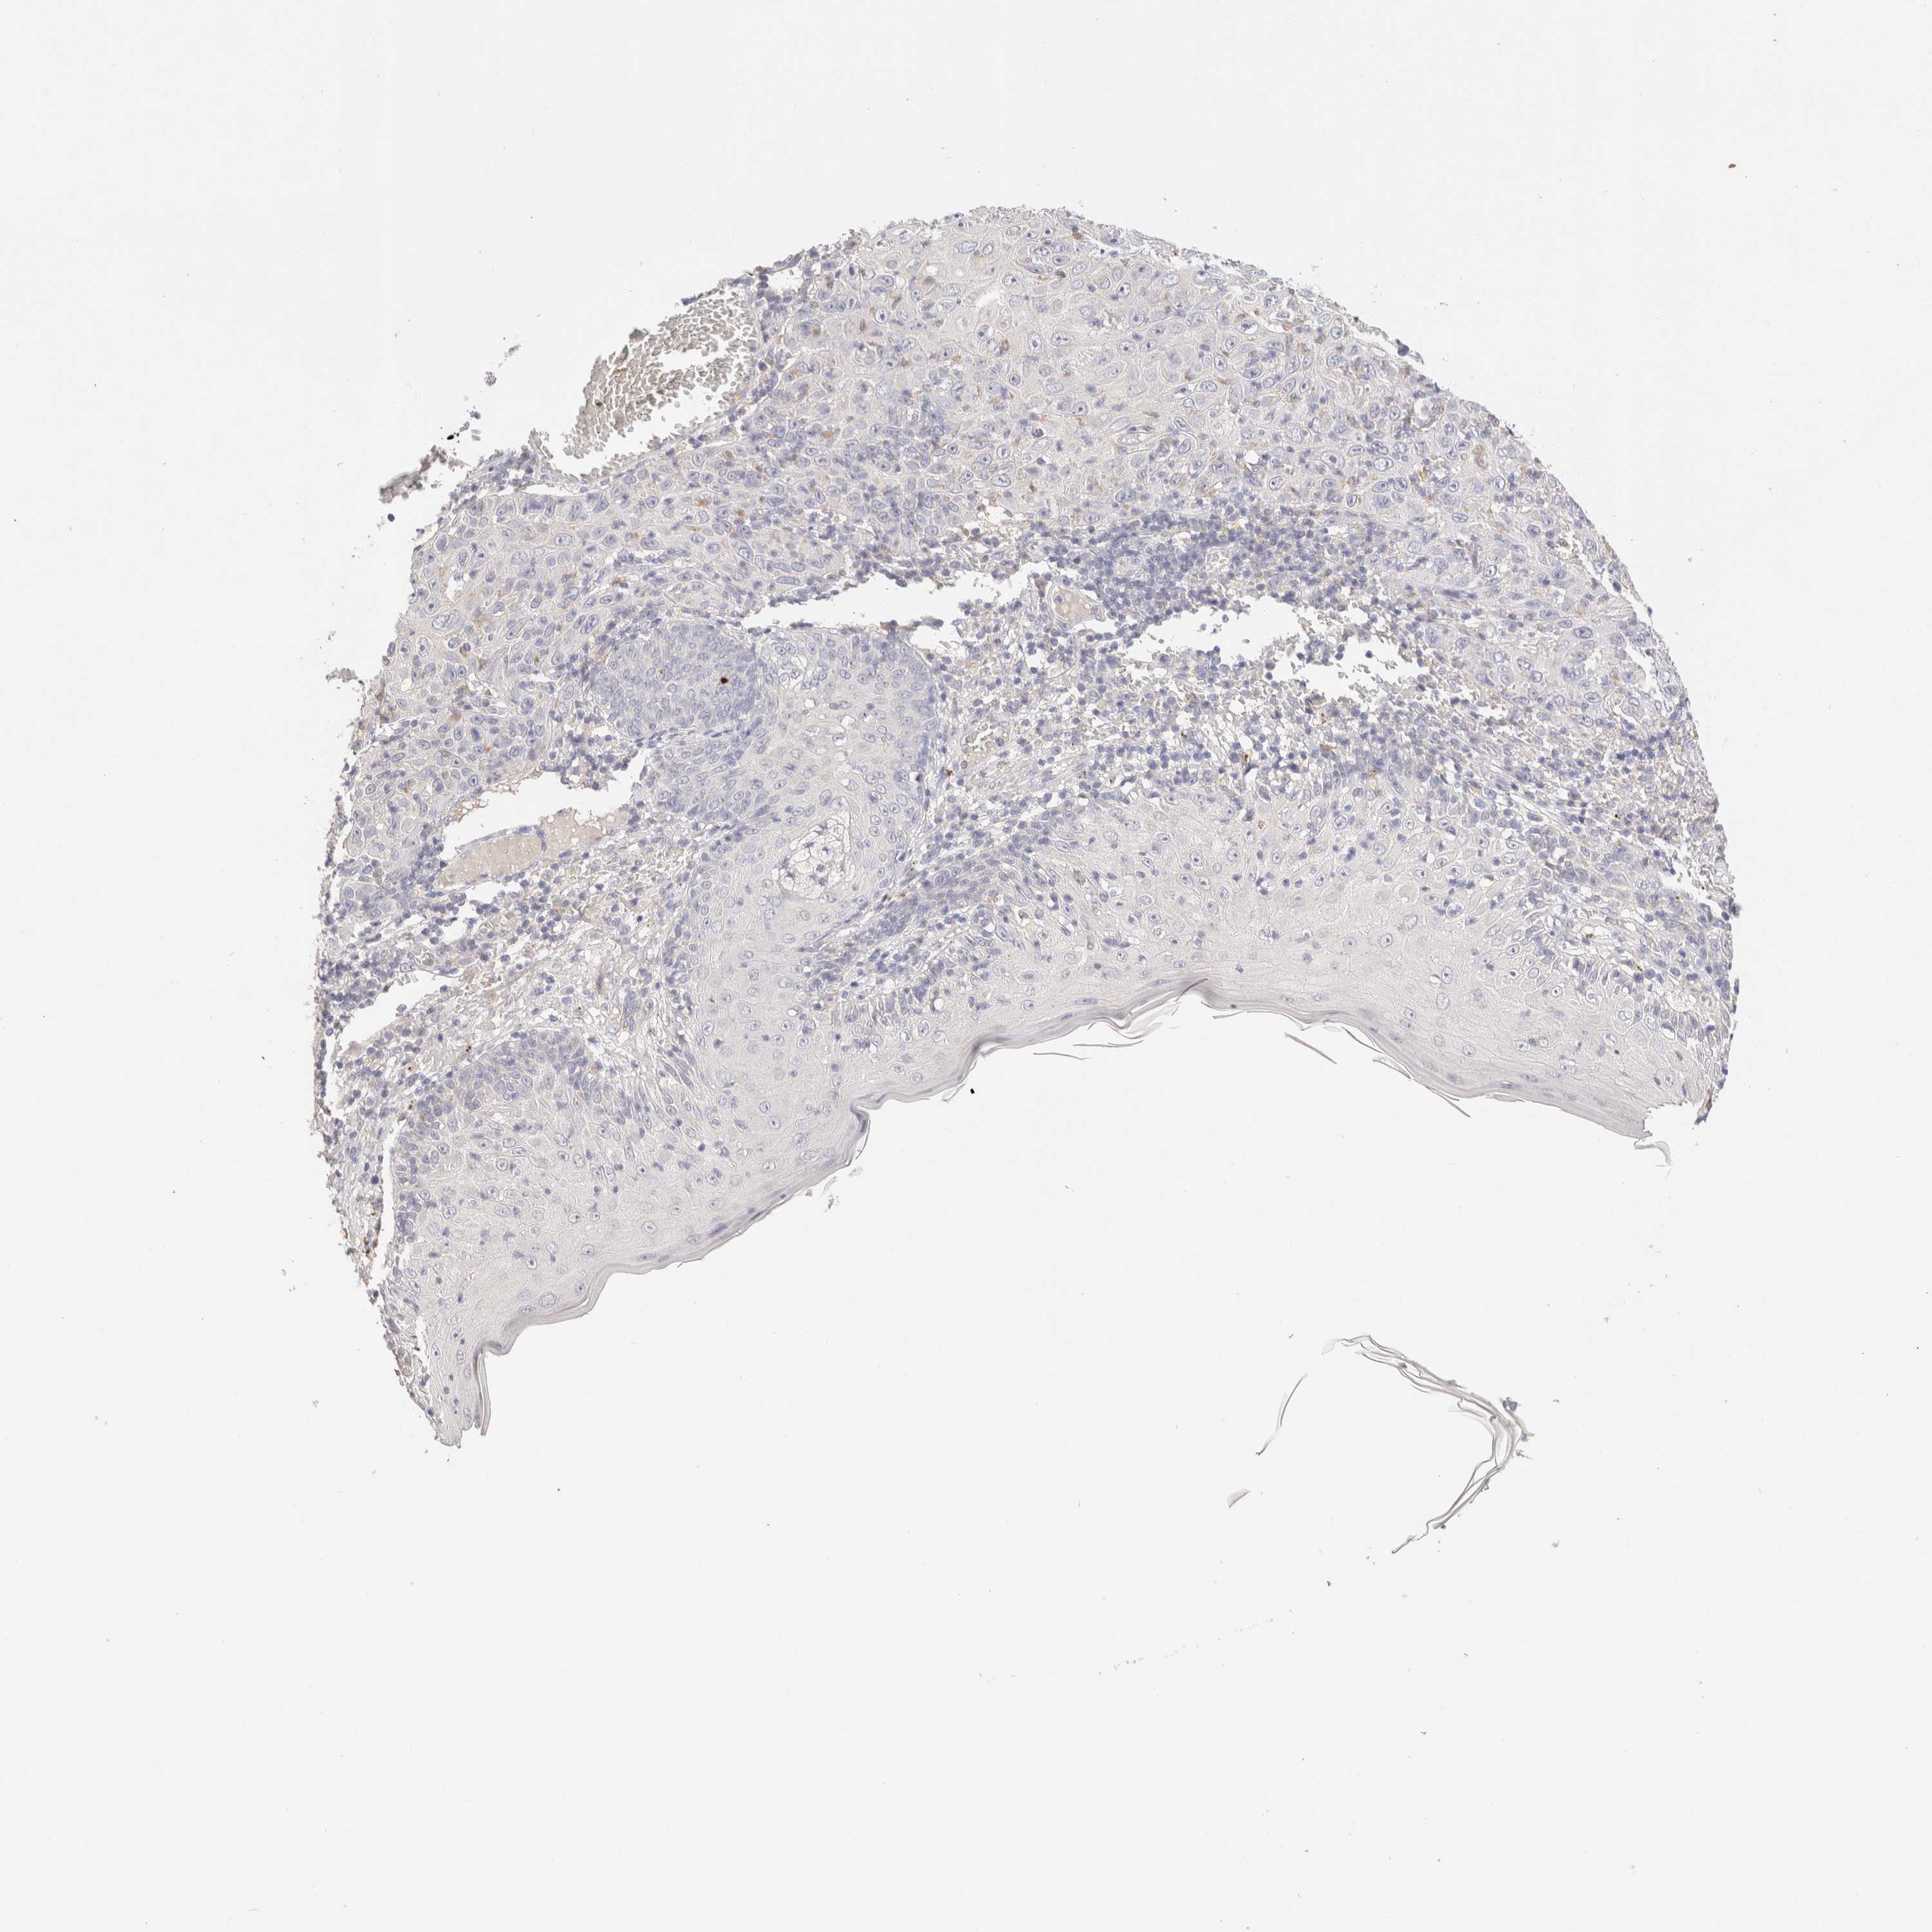

Basal cell and squamous cell cancer

SKIN CANCER - Protein expressioni

A mouse-over function shows sample information and annotation data. Click on an image to view it in a full screen mode. Samples can be filtered based on level of antibody staining by selecting one or several of the following categories: high, medium, low and not detected. The assay and annotation is described here.

Each image is clickable and will lead to virtual microscopy that enables deeper exploration of all samples and also displays staining intensity scores, fraction scores and subcellular localization as well as patient and tissue information for each sample.

Antibody CAB026270

Staining

High

Medium

Low

Not detected

Intensity

Strong

Moderate

Weak

Negative

Quantity

>75%

75%-25%

<25%

None

Location

Nuclear

Cytoplasmic/membranous

Cytoplasmic/membranous,nuclear

Squamous cell carcinoma, NOS